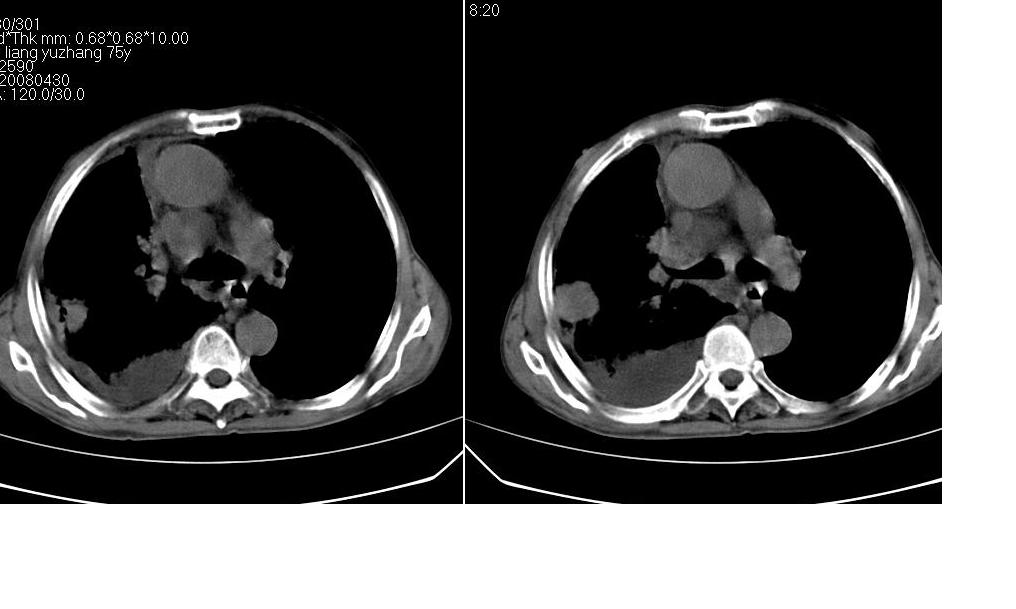

以下是引用zsl6918在2008-5-3 19:53:00的发言:[br]右肺中心型肺癌并纵隔淋巴结转移,胸膜转移,右肺癌性淋巴管炎。

以下是引用liuyue在2008-5-3 20:49:00的发言:[br]1.右侧中心型肺癌伴双肺转移瘤、纵隔淋巴结转移、右侧胸腔积液(侵及胸膜所致可能性大)。[br]2.右肺阻塞性肺炎,癌性淋巴管炎不除外。

以下是引用mzh123在2008-5-3 21:12:00的发言:[br]本人持有不同观点[br]1、右肺似有团块表现,但只有一个层面,所以本人认为还是以片为主,所以不能首先考虑肿瘤[br]2、右肺普遍成纤维化改变 并伴有片状炎症改变,和癌性淋巴管炎表现不同[br]3、所以本人认为是间质纤维化伴感染可能大 及胸腔积液